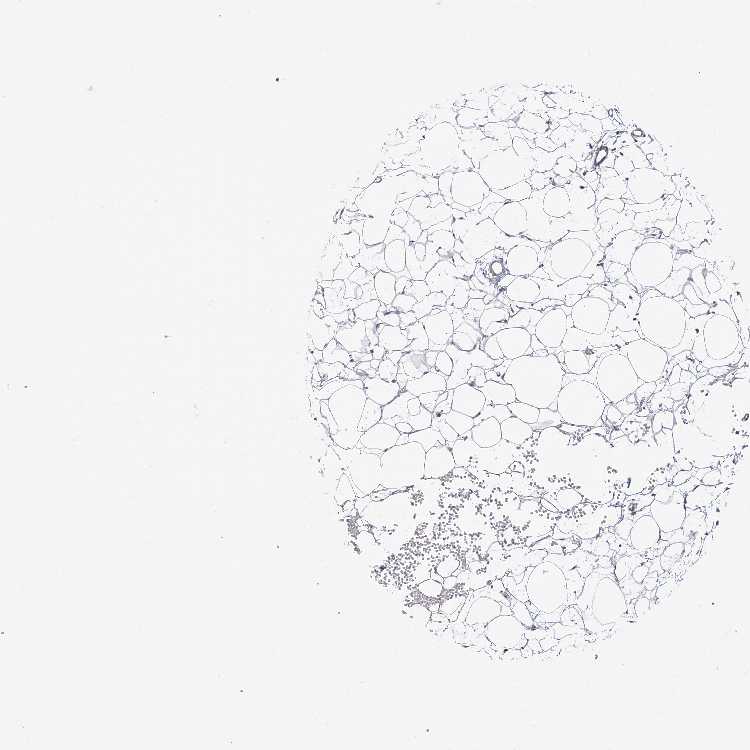

ADIPOSE TISSUE - Antibody stainingi

Antibody staining in the annotated cell types in the current human tissue is reported as not detected, low, medium, or high, based on conventional immunohistochemistry profiling in selected tissues. This score is based on the combination of the staining intensity and fraction of stained cells.

Each image is clickable and will lead to virtual microscopy that enables deeper exploration of all samples and also displays staining intensity scores, fraction scores and subcellular localization as well as patient and tissue information for each sample.

Antibody HPA036394Antibody HPA042024

Adipocytes Not detectedNot detected